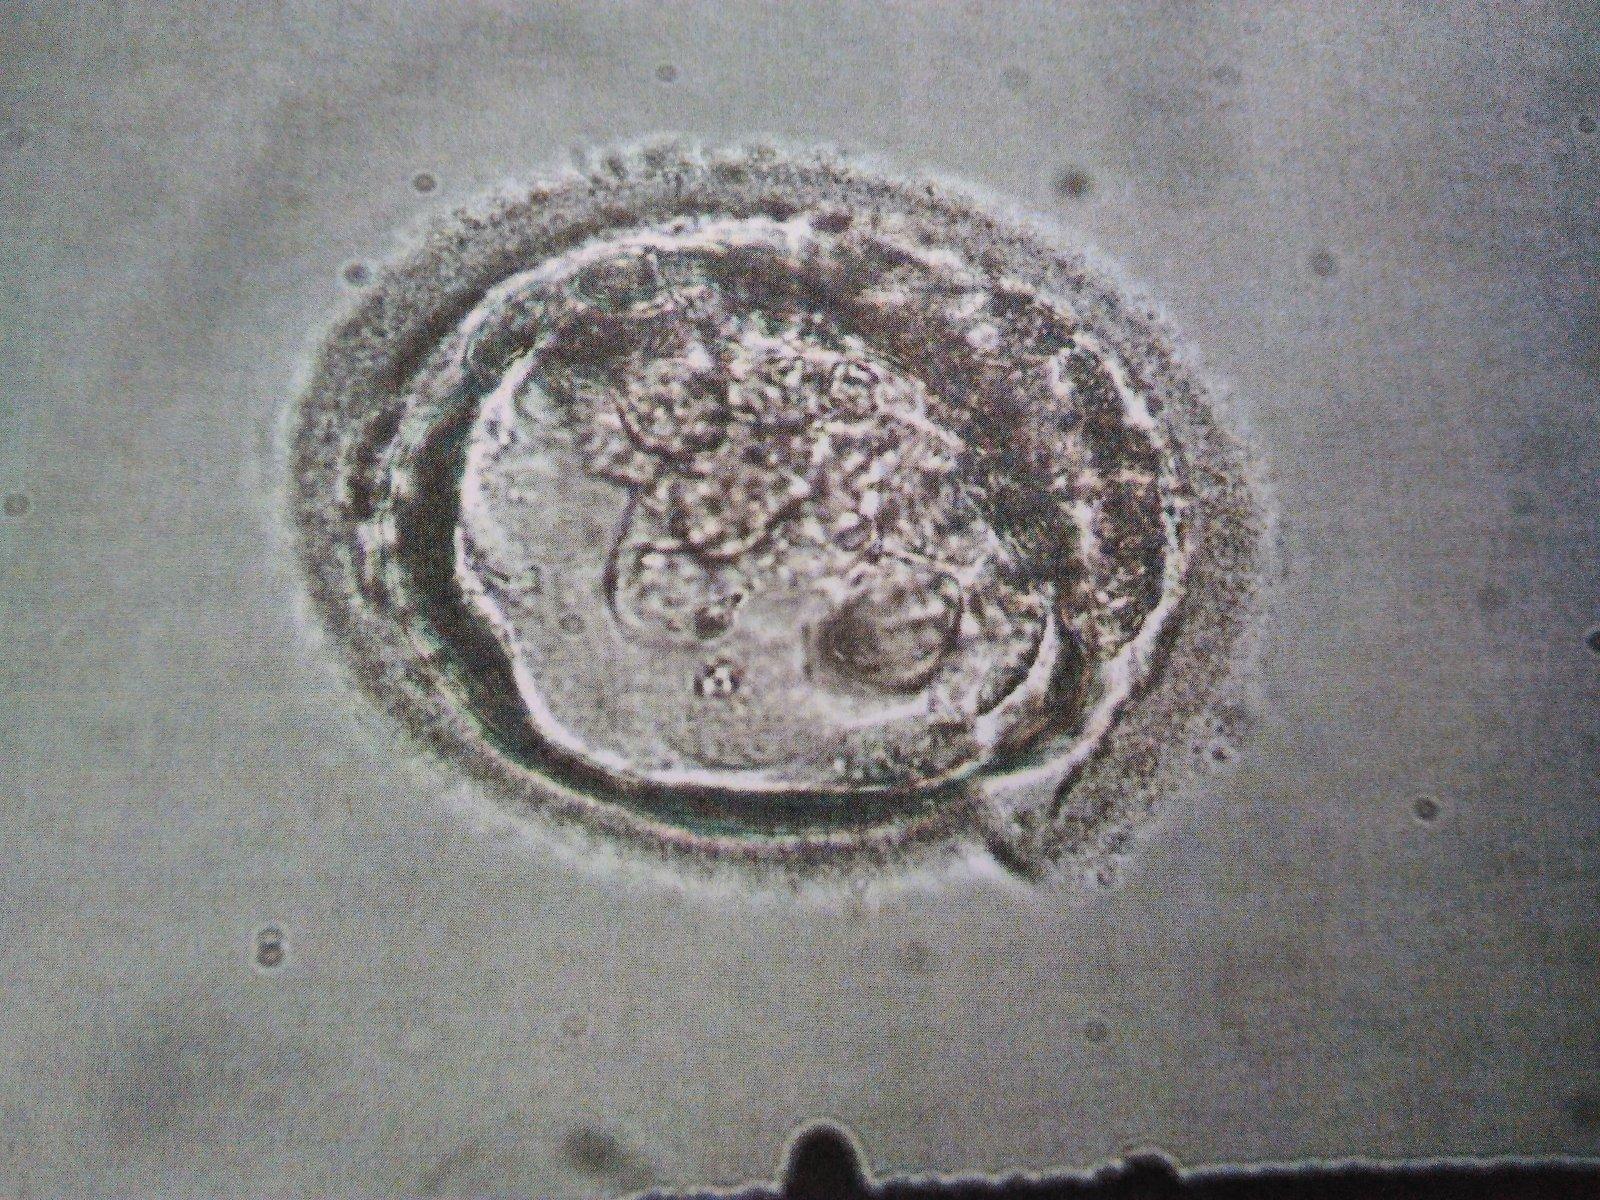

A mam v sobe tecku...💖💖💖 Byl to krasny zazitek videt na ultrazvuku jak to do me dava!!! Jsem dojata jeste ted. Nasazen klidovy rezim a jestli se postesti, brzy na ma vykouknou //...